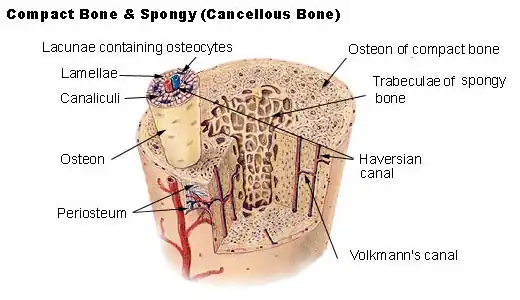

Bone

Bone makes up the skeleton. It consists of two types, cortical and trabecular bone. It will be considered in more detail in its own section.

Cortical or Compact Bone

The thumbnails show calcified and decalcified cross sections of bone. Cortical bone occurs in the shafts of long bones.

Spongy or Trabecular Bone

Trabecular bone appears in vertebrae and the metaphyses (ends) of long bones.